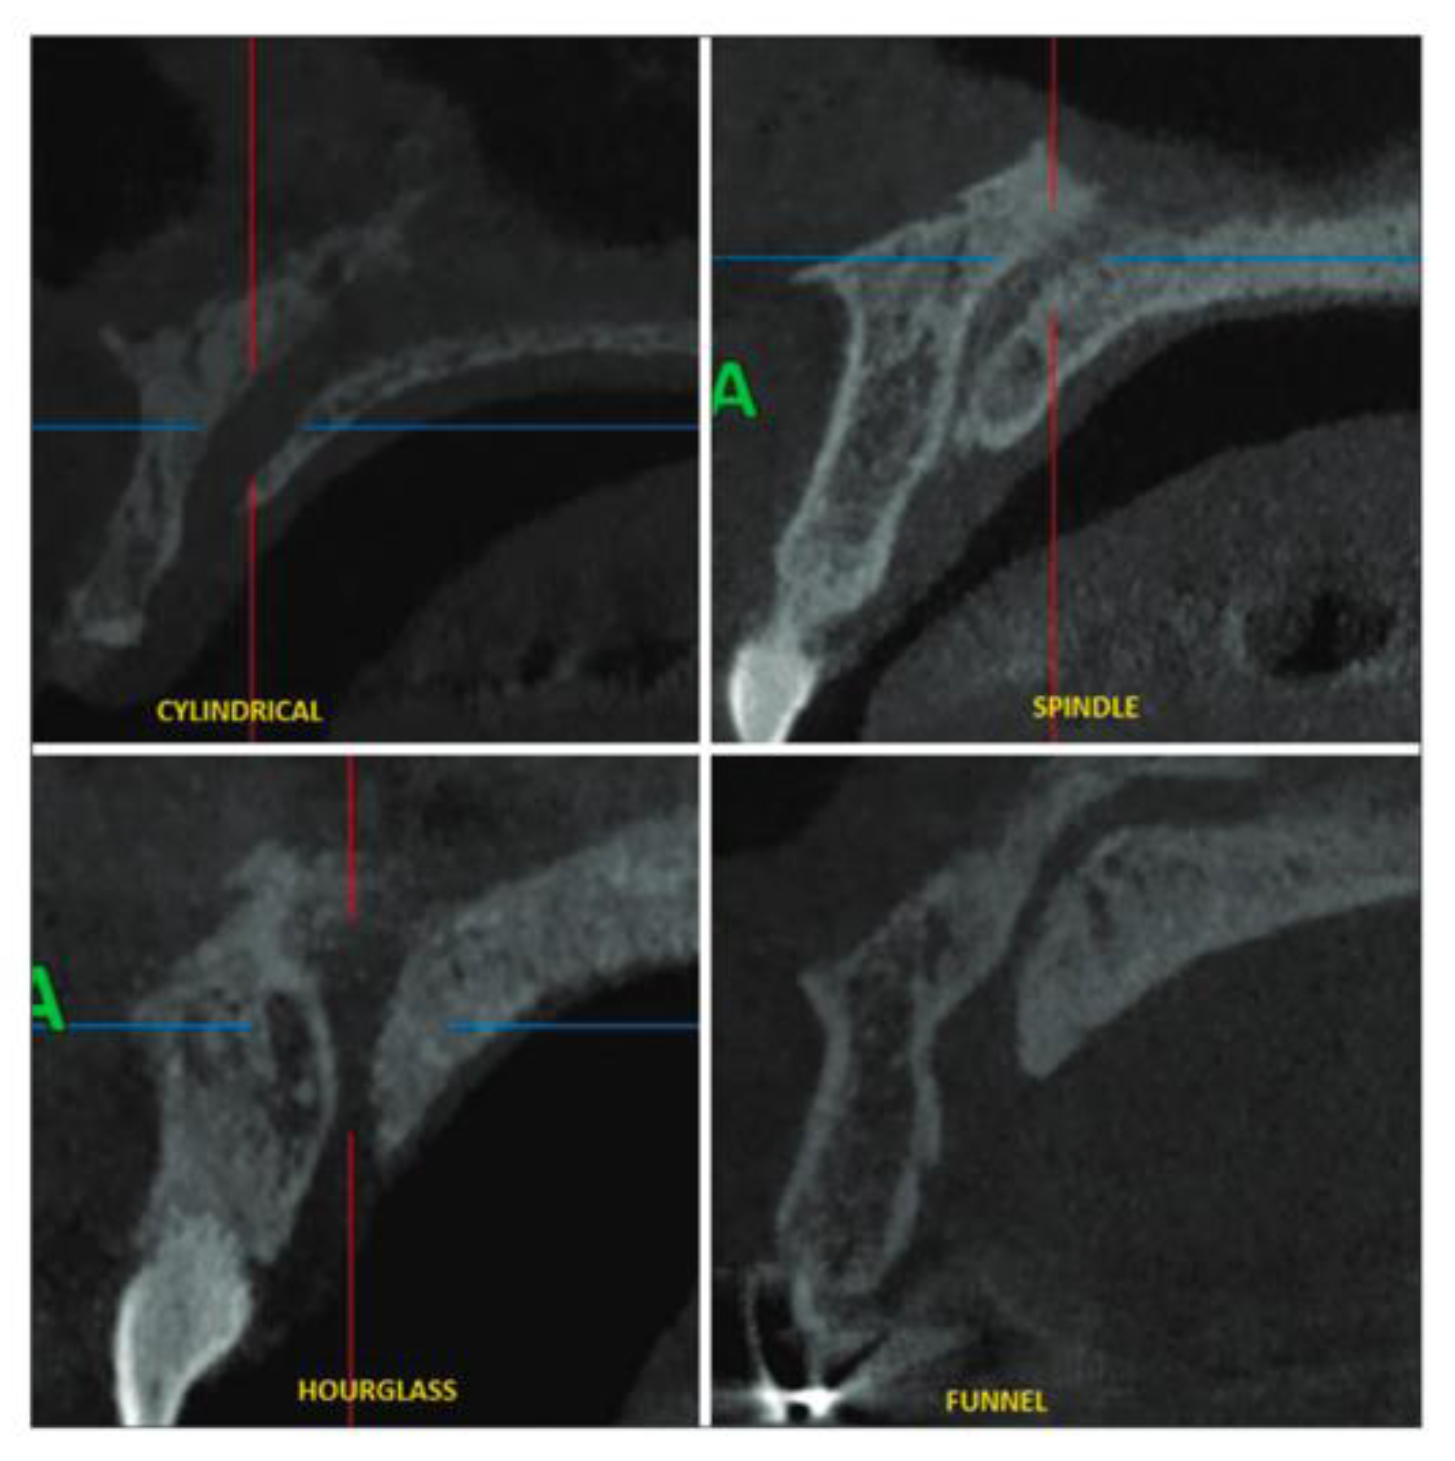

Maxillary Sinus

Septa